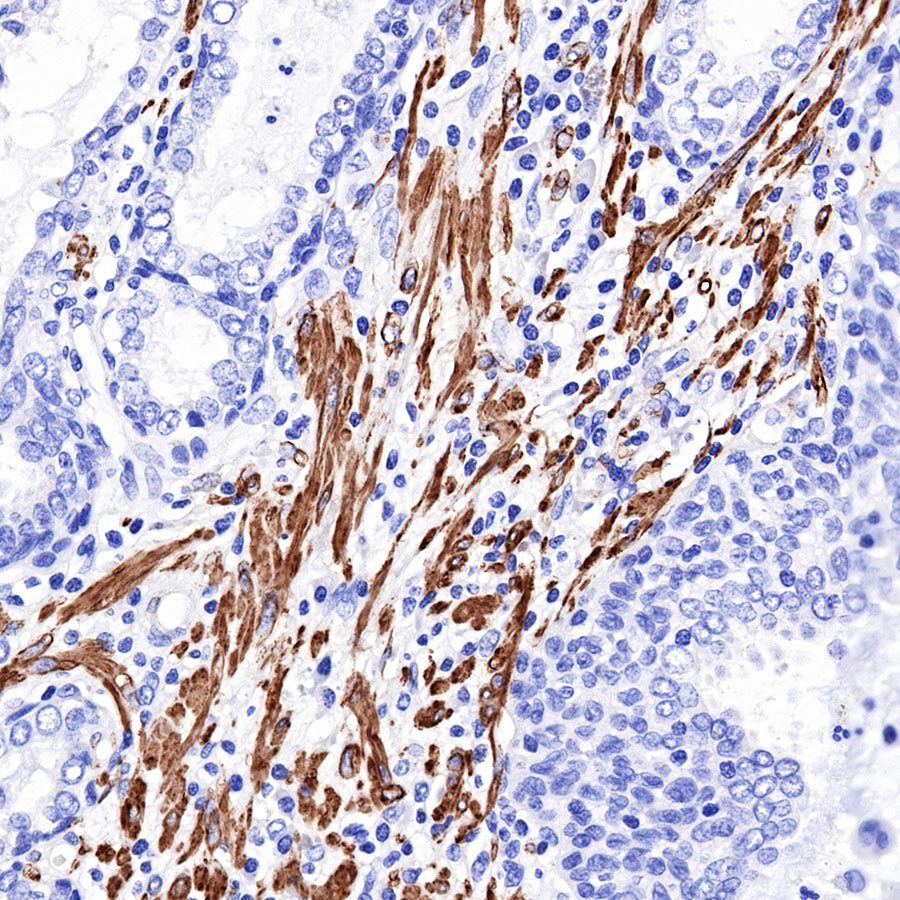

Immunohistochemistry